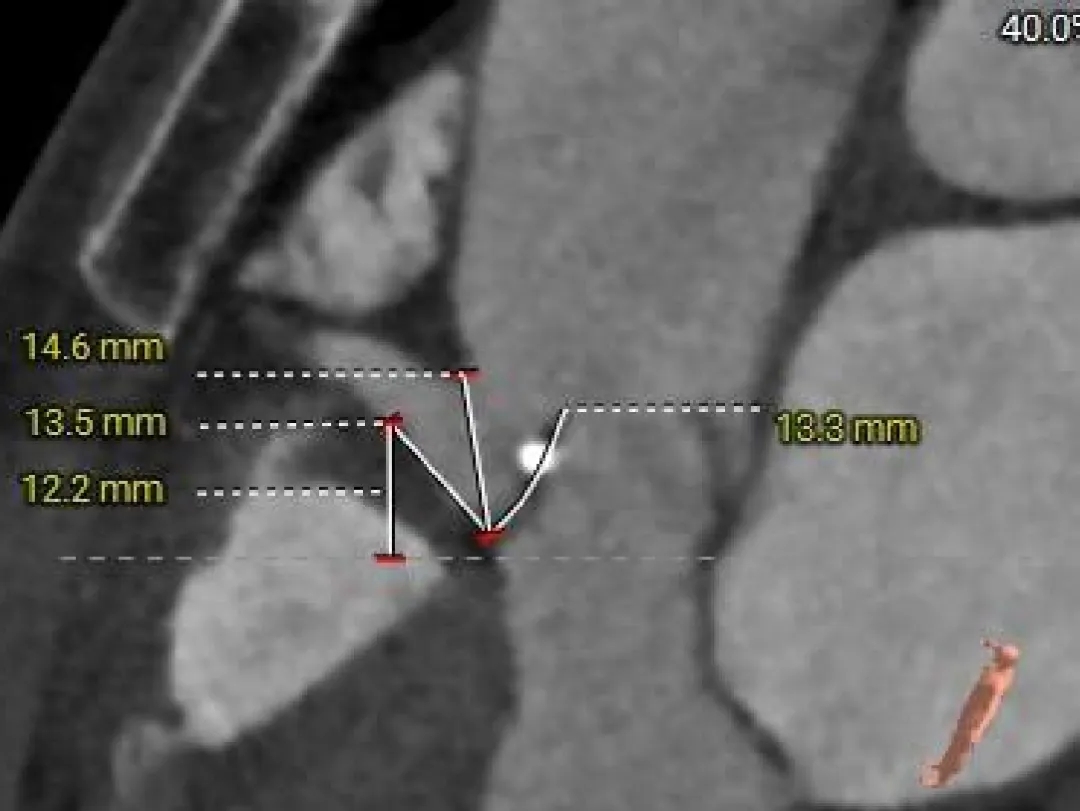

主动脉根部测量

Super-Annulus

2mm 20.5mm

4mm 21.3mm

6mm 21.3mm

8mm 20.8mm

10mm 21.4mm

12mm 20.8mm

Left Coronary

11.5mm

LCA & Leaflet

12.2mm<13.0mm

Right Coronary

10.5mm

RCA & Leaflet

13.3mm<13.5mm